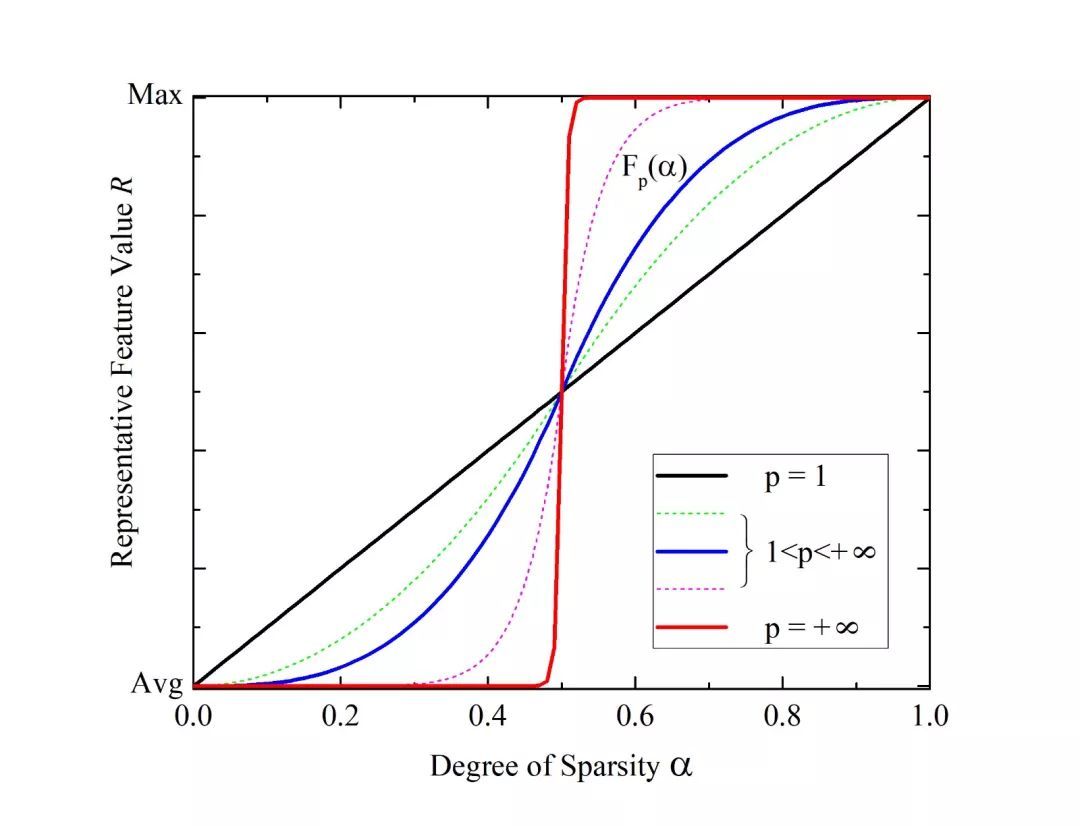

该研究综合了传统的均值、最大值和随机池化算法的优点,提出了一种既可有效保留背景信息,又能突出前景信息并保持较高随机性的新型池化算法。该算法根据特征区域上激活值的稀疏性,利用特殊的可调节控制函数获得相应的特征代表值,再根据该区域内各个激活值与特征代表值在高斯分布上的分布关系进行权值分配。在得到每个激活值的权重后,对其按权重进行随机取值作为池化算法的输出值。最终利用稀疏性随机池化的卷积神经网络来对影像进行特征提取并联结分类器实现分类和识别。该算法不仅能优化特征提取阶段的特征信息,还可避免模型在训练阶段陷入局部最小值,从而增强了识别的泛化性与精度。通过标准数据库的比对发现,利用该算法的深度学习Caffe框架的影像识别精度明显优于传统算法。